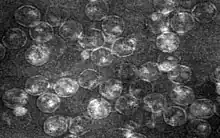

| Equine encephalosis virus virion particles | |